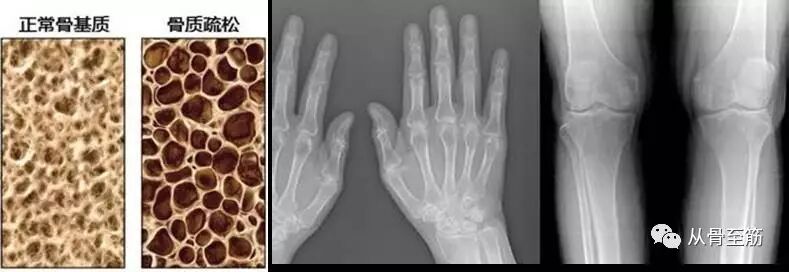

第四:经过制动后,或多或少会存在废用性骨质疏松,活动时也会引起疼痛不适。